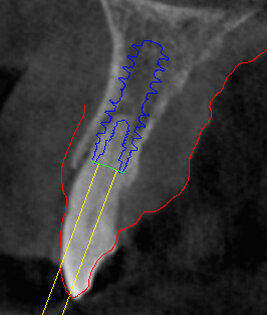

Il piano di trattamento prevede l’estrazione degli elementi dentali, l’inserimento di due impianti e la realizzazione di una protesi fissa di quattro elementi. Il problema da gestire è quello della fase provvisoria. Non è ipotizzabile una protesi mobile e quindi programmiamo di inserire subito dopo l’intervento un provvisorio immediato. Questo ci consente di condizionare da subito i tessuti periimplantari e anche le zone dei ponti. Si rileva un’impronta digitale (Figg. 5, 6), e la programmazione degli impianti viene effettuata con un software di chirurgia guidata (Fig. 7) e la posizione degli impianti nello spazio biologico e nello spazio protesico viene fatta sulla base di una ceratura diagnostica (Figg. 8, 9). Inseriamo gli impianti virtuali nell’osso disponibile (Figg. 10-13) e in relazione all’aspetto protesico correggiamo l’asse di inclinazione degli impianti con componenti secondarie angolate a 17° (Figg. 14, 15). Questo ci consentirà di realizzare una protesi avvitata con i fori situati nella zona palatale.

Fig. 10 - Posizionamento virtuale dell’impianto 1.2.

Fig. 12 - Cross impianto 1.2.